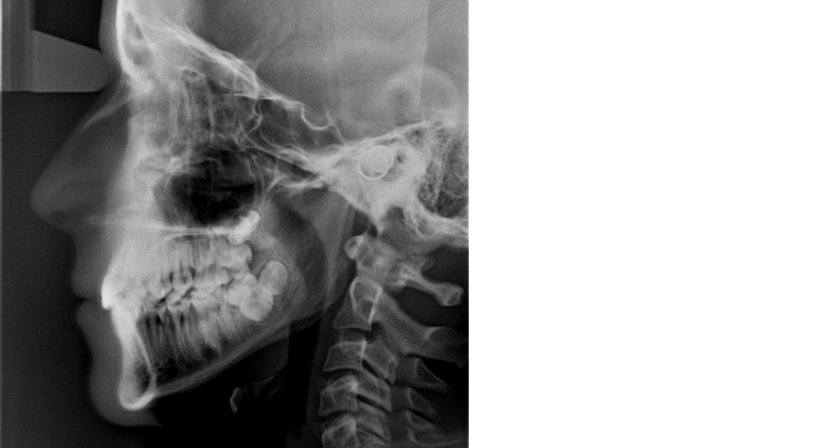

Für die Planung kieferorthopädischer Behandlungen benötigen Zahnärzte spezielle Röntgenaufnahmen. Diese werden in einem bestimmten Abstand mit einer spezielle Halterung und Filter aufgenommen und können vom Kieferorthopäden in Computerprogramme geladen und ausgewertet werden.